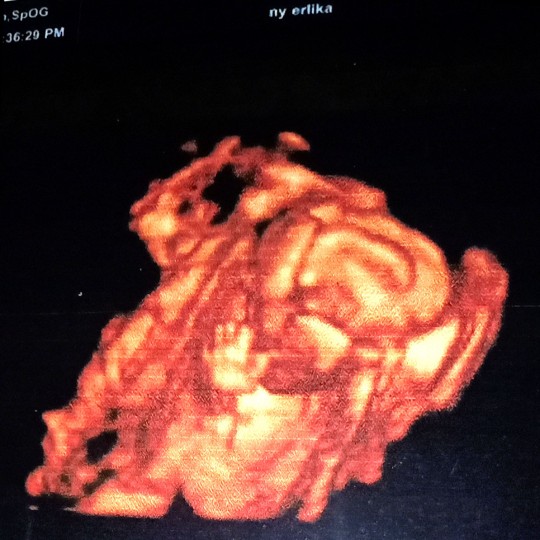

32w